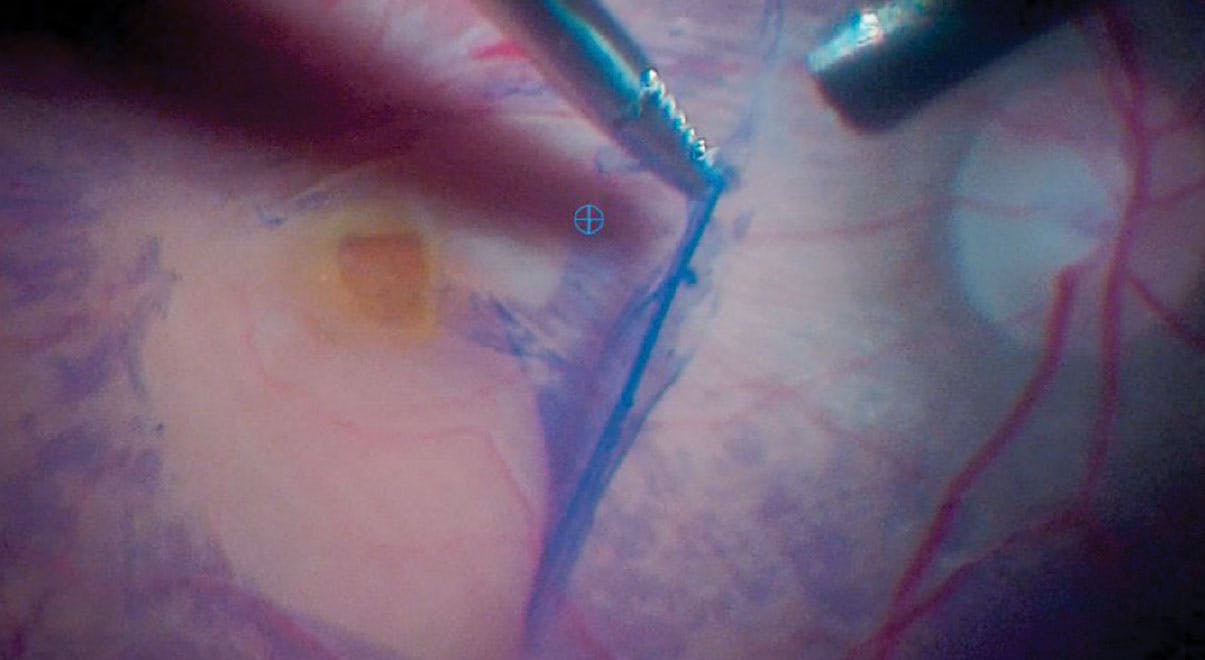

The surgical maneuvers for managing pseudomacular holes can vary based on the specific case, diagnosis, consistency, and tissues involved. When using forceps during retinal surgery (Video 1), it is crucial to hold them halfway open initially to avoid asymmetrical contact with the retina and unintended damage. When peeling the ILM, surgeons should use slow horizontal movements in a clockwise or counterclockwise direction to minimize complications that can arise from vertical traction (Figure). In some cases, loosening the ILM tissue may be challenging because it may be adherent and tense. Closing the forceps’ blades symmetrically, ensuring they remain equidistant to secure a proper grip, potentially offers the retina further protection from trauma. After membrane peeling, surgeons may consider employing a gentle, rhythmic motion with a 25-gauge backflush cannula to clear small hemorrhages from the macular region, particularly in cases with resistant ILM.

Figure. A 25-gauge serrated forceps was used to peel the ILM. The membrane was removed carefully in a counterclockwise direction with a horizontal pull to minimize complications.